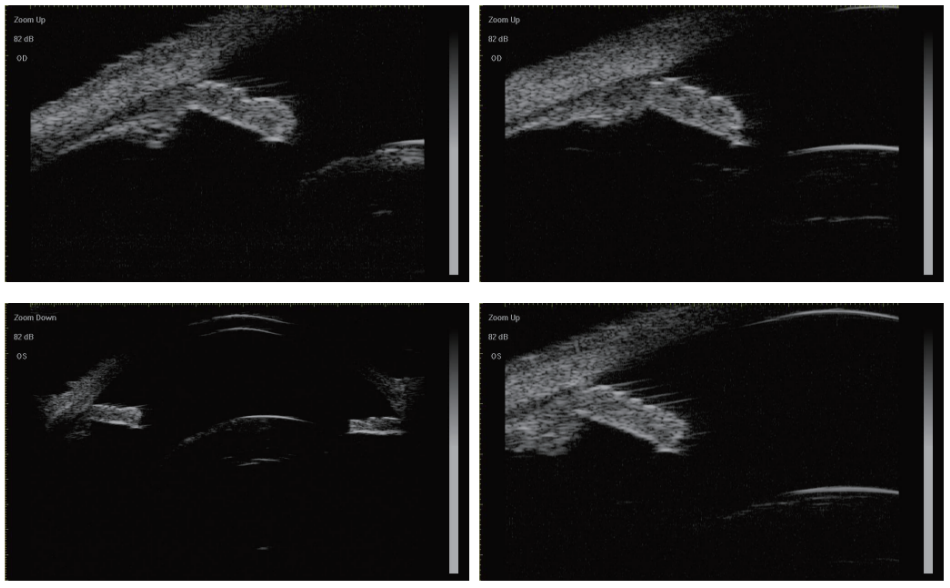

患者,男性,72岁,因“右眼视力下降2年”于2021年1月8日入院。既往史:自幼双眼近视,近视度数逐年加深,近2年患者自诉双眼配镜-10 D,仍无明显视力改善。否认家族遗传病史。体格检查:体态匀称,一般情况良好,发育正常,脊柱四肢无畸形。眼部检查:右眼视力:0.06,矫正无效,左眼视力:0.05,-12.00 DS/-2.50 DC×170= 0.30,眼压:右眼:17.9 mmHg(1 mmHg=0.133 kPa),左眼:18.1 mmHg。右眼结膜无充血,角膜透明,前房深,虹膜震颤,瞳孔圆形居中,晶状混浊C2N4P1,向下方脱位,晶状体震颤明显,余眼部情况窥不清(图1)。左眼结膜无充血,角膜透明,前房深,瞳孔圆形居中,晶状体混浊C2N3P1,360°悬韧带松弛,向后方及颞下方脱位,余眼部情况窥不清。眼部B超示:双眼内异常回声,玻璃体浑浊伴后脱离可能,轻度后巩膜葡萄肿可能。双眼OCT示:隐见左眼黄斑视网膜前膜,右眼中心凹形态可。超声生物显微镜(UBM)示:双眼前房不浅,各方位房角开放。右眼上方,左眼上方、内侧及鼻上悬韧带缺失,睫状突-晶状体间距增大,右眼玻璃体疝至瞳孔区,余方位悬韧带稀疏伴部分缺失。双眼晶状体直径小,前后表面较突(图2)。眼部A超(IOL Master 700)示:右眼:晶状体厚度 5.41 mm,眼轴 25.82 mm,角膜曲率K1 43.06 D,K2 43.93 D。左眼:晶状体厚度 5.27 mm,眼轴 25.30 mm,角膜曲率K1 42.98 D,K243.65 D。心电图:窦性心律、T波改变。诊断:球形晶状体、晶状体不全脱位、并发性白内障、高度近视。使用Haigis公式计算人工晶状体度数,术前规划术后目标屈光度-2 D近视。

图 2 术前双眼超声生物显微镜 (UBM) 提示双眼球形晶状体伴晶状体半脱位

Figure 2 The preoperative ultrasound biomicroscopy (UBM) images illustrated bilateral microspherophakia accompanied by ectopia lentis